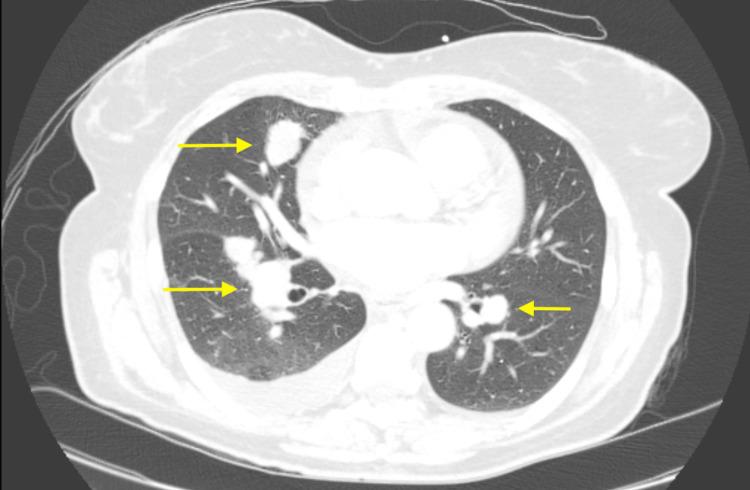

Sclerosing epithelioid fibrosarcoma (SEF) is an extremely rare subtype of sarcoma that appears histologically low-grade yet usually has a clinically aggressive course with a high rate of local recurrence and distant metastasis. However, these recurrences and metastases often occur years after initial treatment. Metastases can be to the lung as well as extra-pulmonary sites. In this case report, we discuss a patient who developed SEF in the deep soft tissue with metastases. This patient underwent checkpoint inhibitor therapy, with disease response. Thus, SEF is a sarcoma subtype with a unique tumor biology, and immunotherapy may be a promising avenue for treatment.

硬化性上皮样纤维肉瘤(SEF)是一种极其罕见的肉瘤亚型,其组织学表现为低级别,但临床过程通常具有侵袭性,局部复发率和远处转移率较高。然而,这些复发和转移往往在初始治疗数年之后才会出现。转移部位可以是肺部以及肺外部位。在本病例报告中,我们讨论了一名在深部软组织发生SEF并伴有转移的患者。该患者接受了检查点抑制剂治疗,并出现了疾病反应。因此,SEF是一种具有独特肿瘤生物学特性的肉瘤亚型,免疫疗法可能是一种有前景的治疗途径。